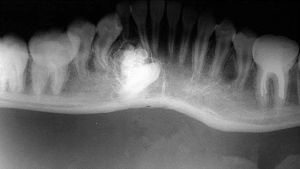

3.X線攝片示骨質膨脹,有很多大小形狀不同、發育不全的影像,或透射度似牙組織的一團影像,影像與正常組織間有一條清晰陰影,為牙瘤的被膜。